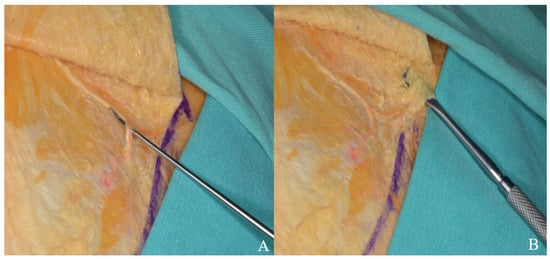

Is a Bacteriophage Approach for Musculoskeletal Infection Management an Alternative to Conventional Therapy? -